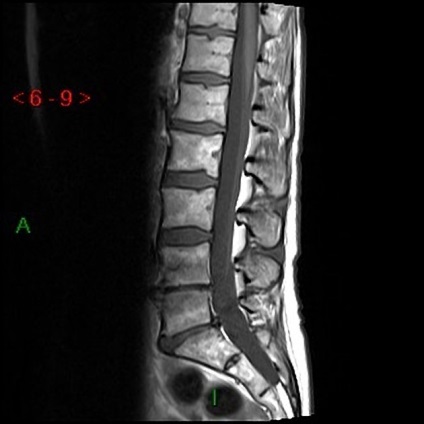

MRI az ágyéki gerinc keresztcsonti

Mágneses rezonancia képalkotás minden gerinc kezdődik egy gyors vizsgálat a sagittalis síkban gradiens echo. Ez a szakasz a vizsgálat mindössze 10-30 másodperc. Ezután, hogy a készítmény a T-1 és T 2 súlyozott tomogramok sagittalis és axiális síkban.

A tanulmány a gerinc szerkezete optimálisan elvégezni T1-WI. A képadatok által meghatározott gerincvelő, mint egy homogén struktúra egy hiperintenzív jelet. Subarachnoidális térben és szalagok alacsony jel intenzitását. A jel a csigolya egy inhomogén szerkezetű: kompakt csontanyagot a csigolyatestek és folyamatok, körgyűrű és végtárcsák hypointense jelet csontvelő csigolyatestek olyan jelet állít elő a mérsékelt intenzitású. Csakúgy megkülönbözteti egy lófarok vizsgál.

Jellemző értékei MRI ágyéki gerinc: a méret a dura sac 12-15 mm (elöl-hátul dimenzió), gerinccsatorna szélessége 21-29 mm (csatorna bővítése fokozatosan történik az egész).

Osteochondrosis - destruktív folyamat a gerinc. Túlnyomórészt befolyásolja ágyéki és gerinc területeken. Ez okozta, két lábon járó mozgásszervi és fokozott terhelés ezen osztályok. MRI lumbosacralis gerinc talált: ellaposodása a fiziológiás görbék a gerinc, csökkentik a magassága a porckorongok, lemez meszesedés kiálló élek, alkotó sérv, csökkenti a jelintenzitást a T2 csigolya-VI.

A megjelenése a porckorong sérv lehet bármely területén a gerinc gyakran érintett több osztály. A leggyakrabban érintett ágyéki csigolyák és a lemez közötti ágyéki csigolya és az első keresztcsonti. MRI lumbosacralis gerinc határozza gryzhepodobnaya dudor a csigolyaközi térben, amelynek ugyanolyan intenzitású, mint porckorongok.